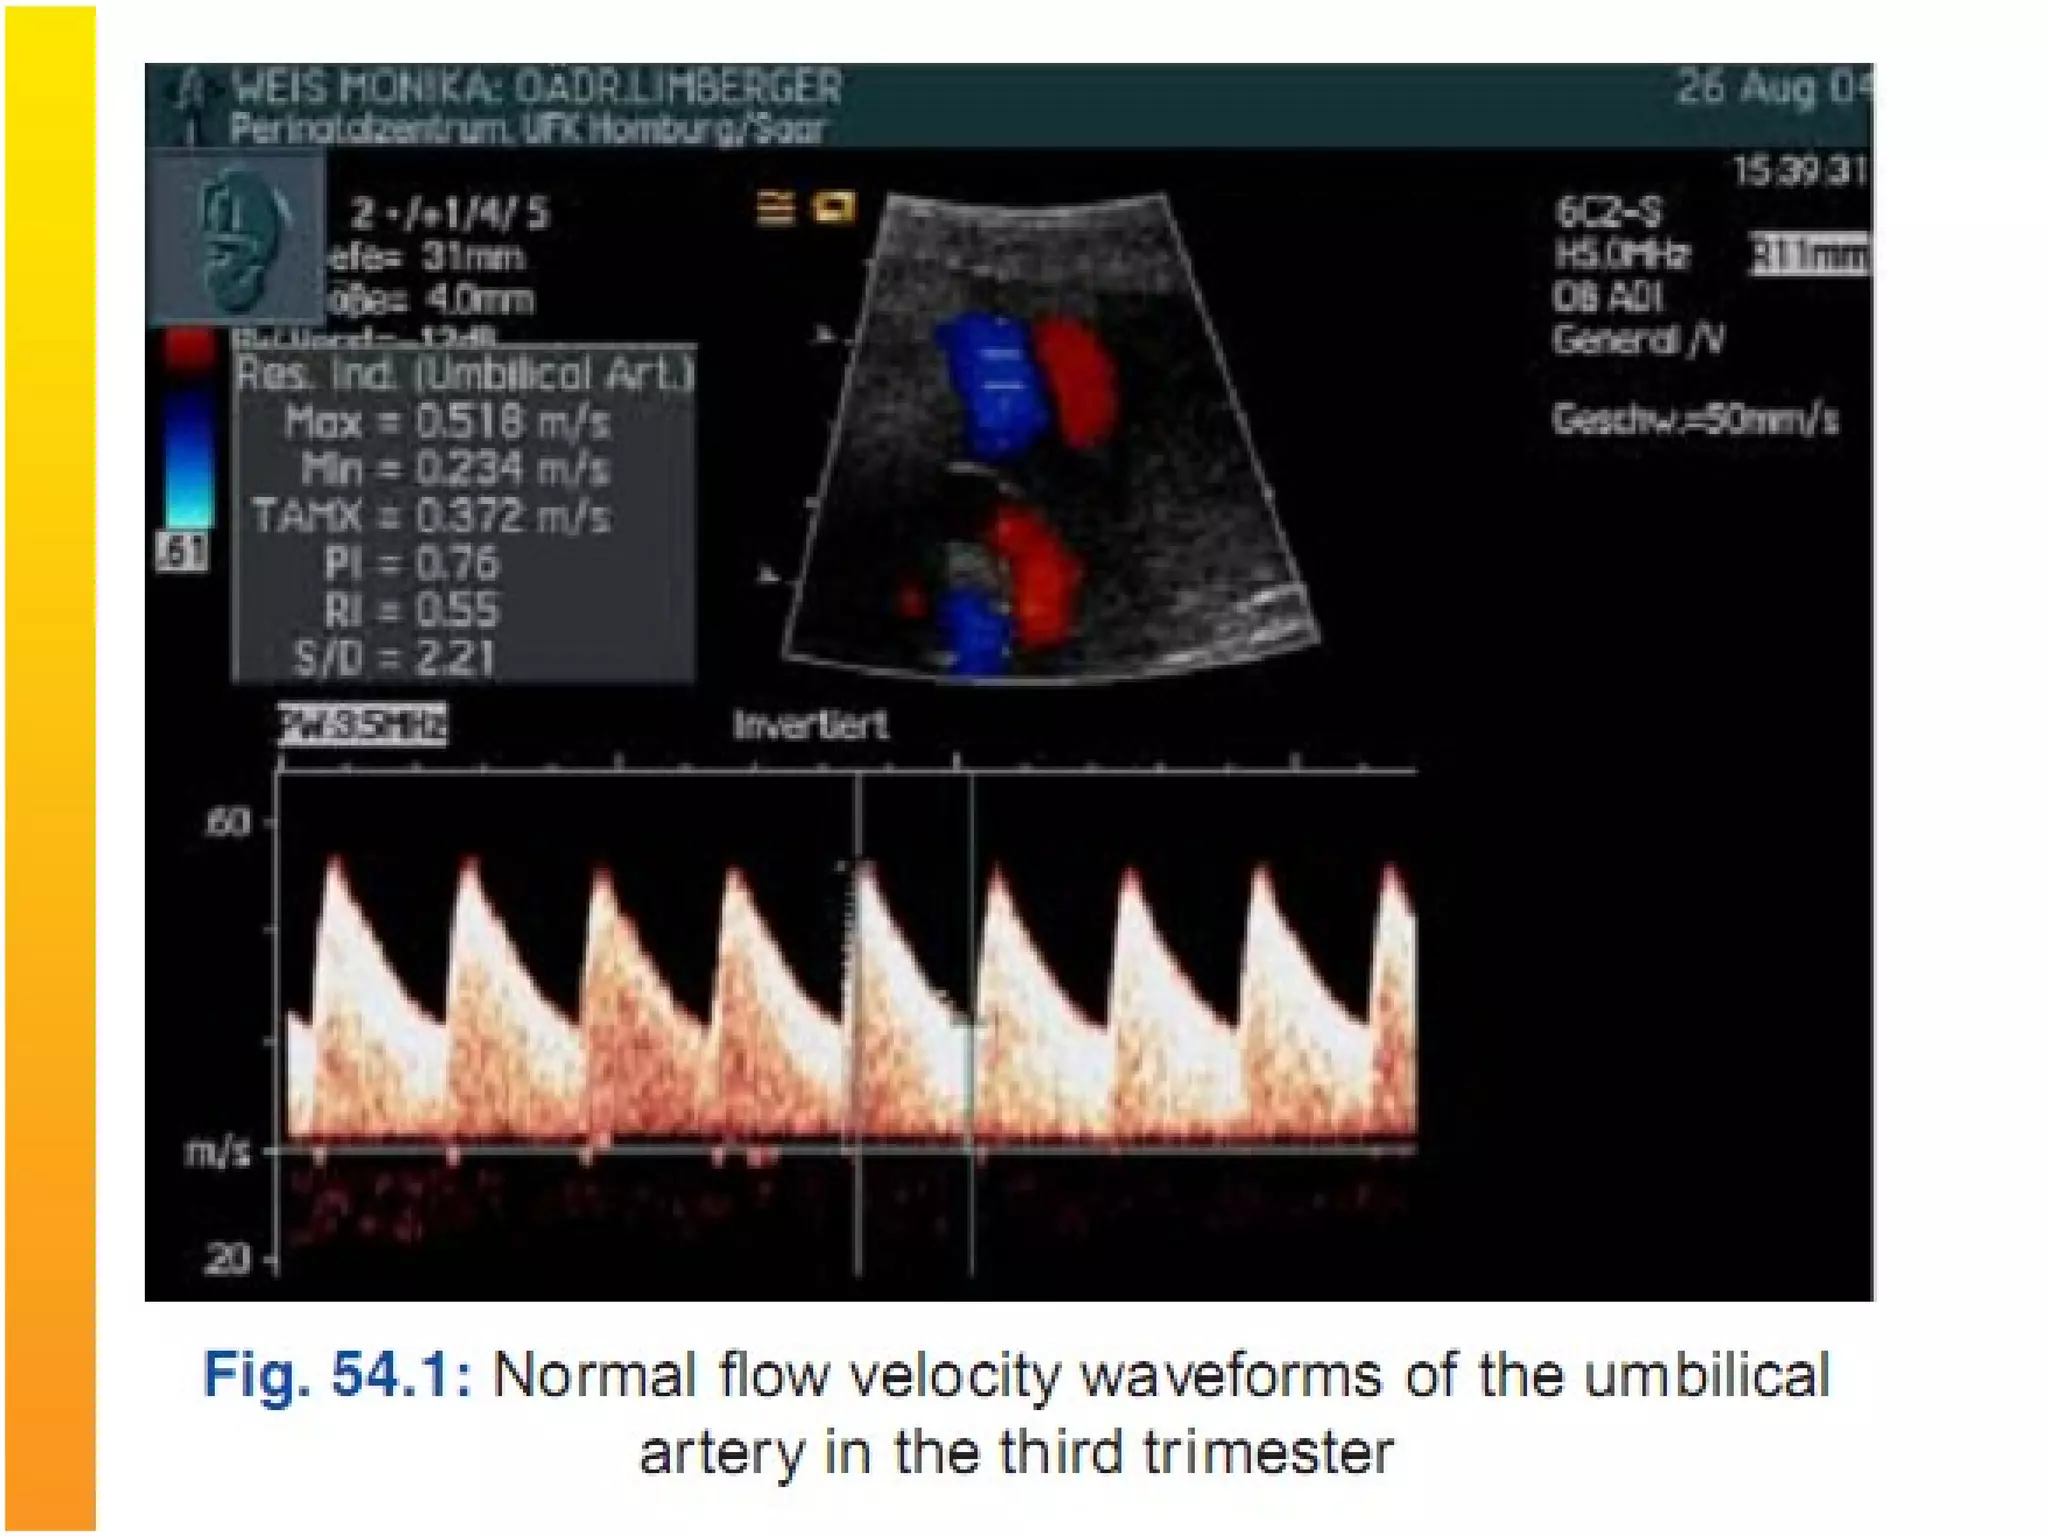

3. Doppler Ultrasonography: doppler flow studies are

Most widely used arterial indices are :

Pulsatility index (PI): Systolic and diastolic peak

velocity / time averaged maximum velocity

Resistance Index(RI): Systolic and diastolic peak

velocity/ systolic peak velocity

Systolic to diastolic ratio(S/D): Systolic peak velocity /

diastolic peak velocity

Umblical Artery doppler- In IUGR there is

increased umblical artery resistance (increased

S/D ratio), absent end diastolic flow and finally

reversed end diastolic flow.

Perinatal mortality rate increases significantly in

fetuses with absent end diastolic flow (9-41%)

and reversed end diastolic flow (33-73%) in

umblical artery.